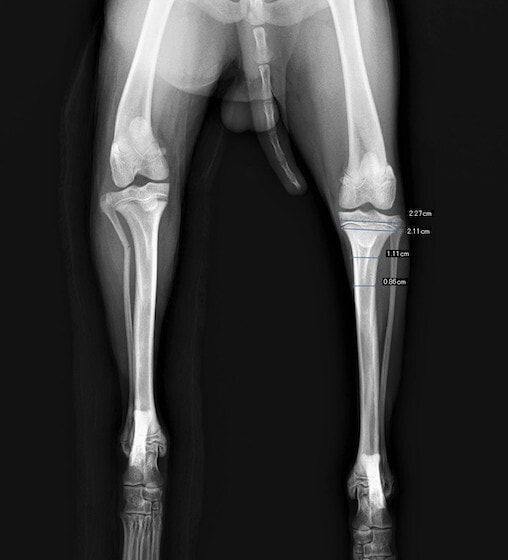

症例3:キルシュナーワイヤーのピンニングによる整復

ペルシャ猫 11ヶ月齢 雄

他院にて左大腿骨遠位の成長板骨折(salter-harrisⅠ型)が認められており、治療相談を目的として来院。当院にて、キルシュナーワイヤーを用いたピンニングにより骨折部位の整復を行いました。術後の経過は良好で、現在も経過観察中です。

術前レントゲン